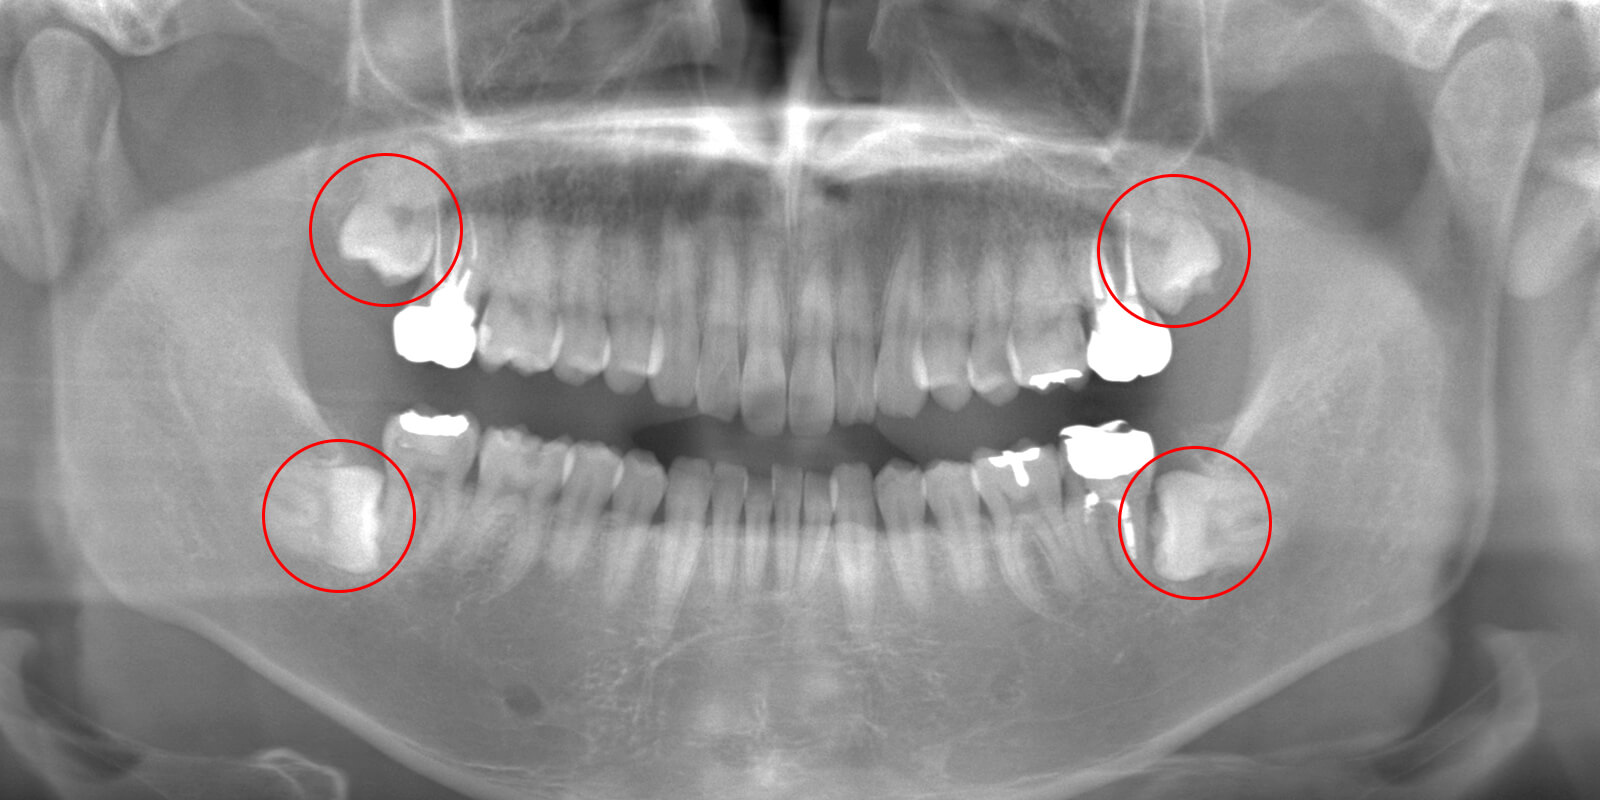

通常は「2次元」で撮影するレントゲンを使用して診断を行いますが、当院では「3次元」での撮影が可能なCTを用いてより詳細な診断を行います。

2次元と3次元では「見える範囲」が異なります。

下の画像は他の治療のケースですが、同じ部位を2次元レントゲン(左)、3次元のCT(右)で撮影したものです。

丸がついている部分が問題の生じている部分で、3次元ではしっかり黒い影が見えますが、2次元ではそれが確認できません。

簡単にまとめると、2次元レントゲンだけでは「問題が見落とされる」可能性があるということです。

歯科医療では、「見える」「見えない」が大きな違いを生みます。

当院では、しっかりとした視野を提供する3次元のCT装置を使って診断を行っています。